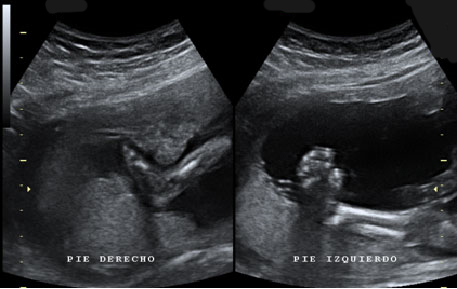

Las ecografías en 2D y en 3D en la semana 20 de embarazo permite diagnosticar algunas malformaciones congénitas fetales, como el labio leporino, que se visualiza en estas imágenes.

Labio leporino (*)

Visualización del mismo caso con ecografía 2D (izquierda) y con ecografía 3D (derecha). La imagen más evidente en la ecografía 3D hace más comprensible para los padres el alcance del problema.